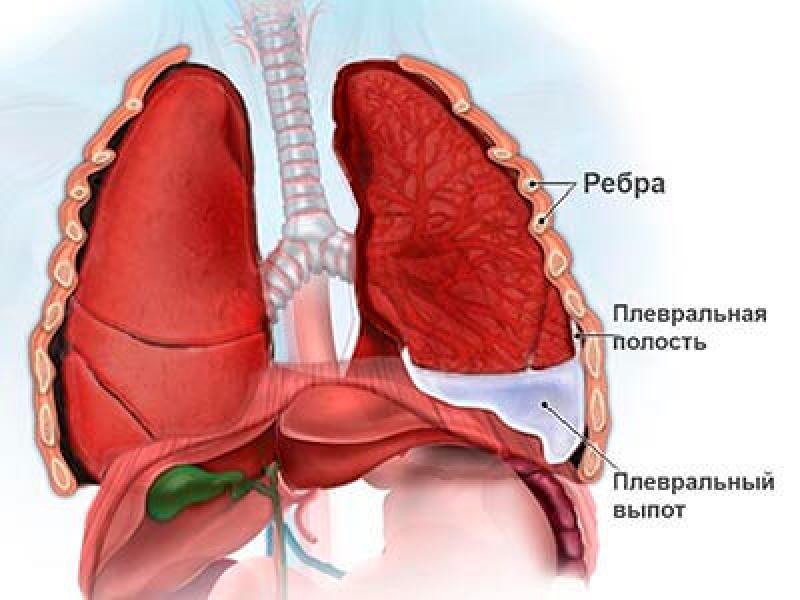

Диагностика плеврального выпота: что нужно знать